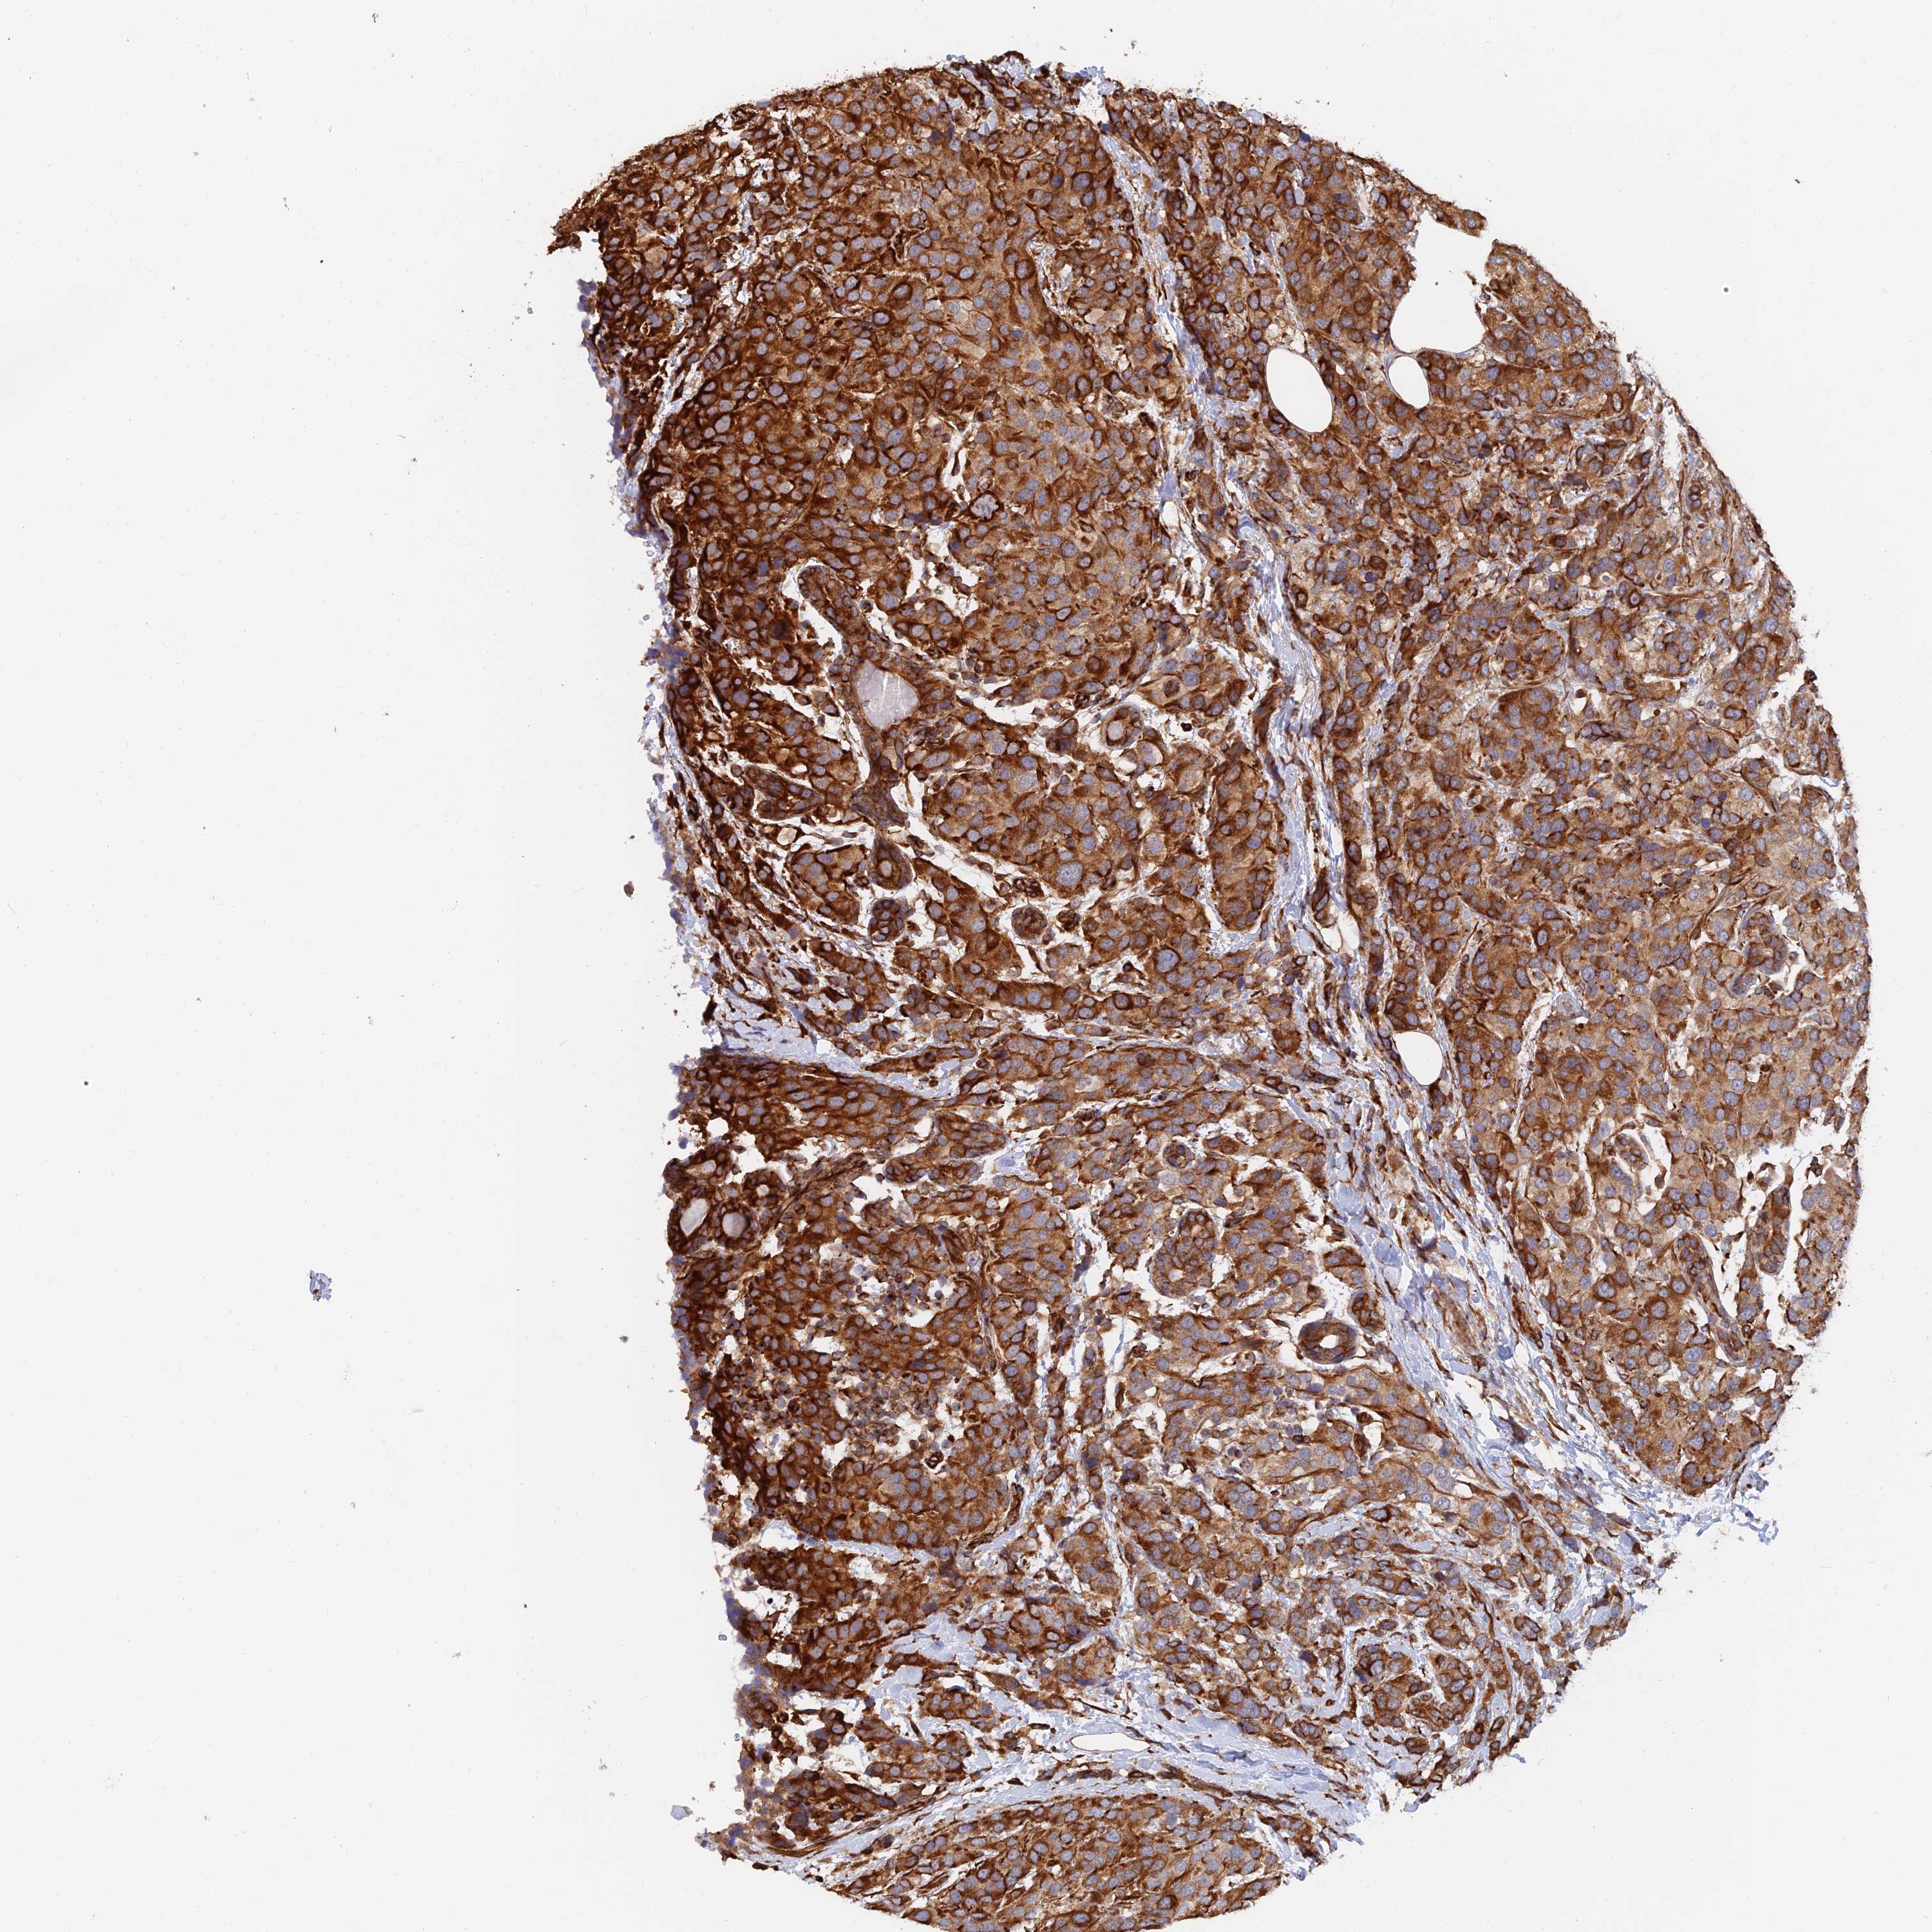

CANCER BREAST CANCER Show tissue menu

BRCA TCGA BRCA VALIDATION PROTEIN EXPRESSION